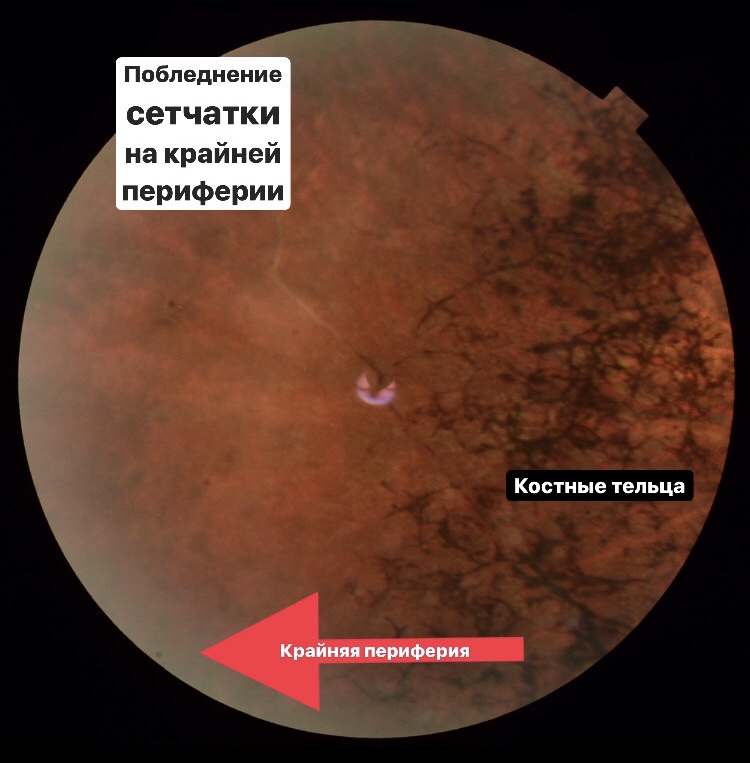

- все материалы (фото фундус камеры, сканы ОКТ взяты из личной практики и разобраны для Вас лично мной) - это ЧЕСТНО! А здесь только так!

- видео, сканы ОКТ с обозначениями, фото глазного с разбором на детали, аудисопровождение, текст и, конечно, ОБУЧАЩИЕ ТЕСТЫ